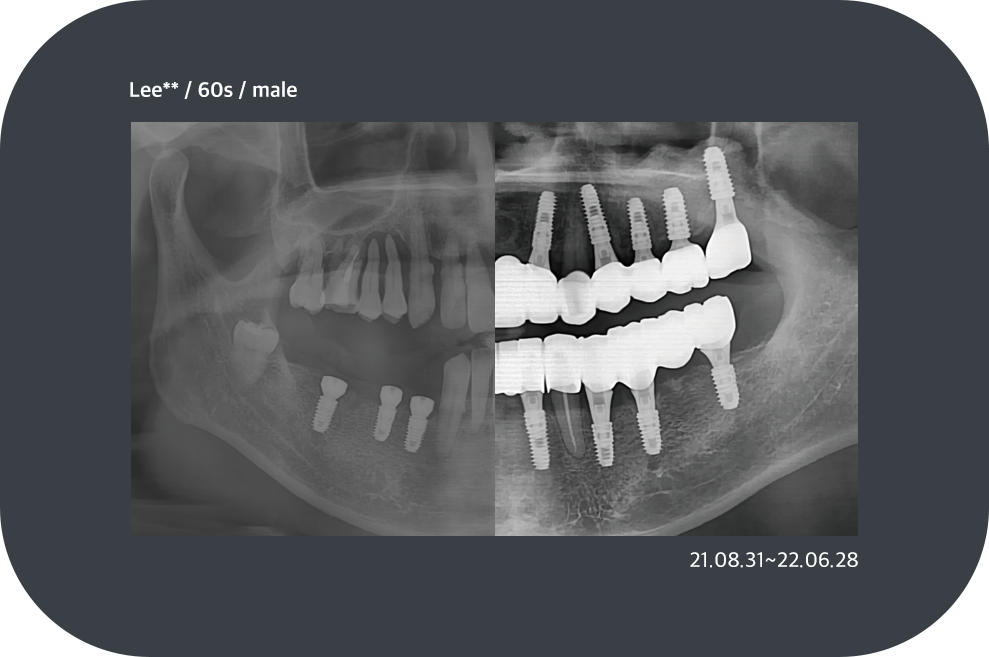

전체 임플란트

충치, 잇몸질환, 사고 등의 이유로

치아가 전부 상실된 경우

고정식으로 치아를 모두 재현하는 시술로 기능 회복 뿐만 아니라

전반적인 상황을 고려해야 하므로 경험이 많은 시술자에게 받아야 합니다.

치료사례

임플란트 치료사례

*모든 증례 사진은 의료법 제23조, 제56조에 의거하여, 당사자의 동의하에 게시하였습니다.

*치료 사진은 모두 본원에서 치료한 환자분의 사진입니다.

*치료 사진은 모두 동일인의 사진이며, 동일조건에서 촬영하였습니다.

*개인의 차이에 따라 시술 및 수술 후 부작용이 발생할 수 있으며, 의료진과 충분한 상담을 받으시기 바랍니다.